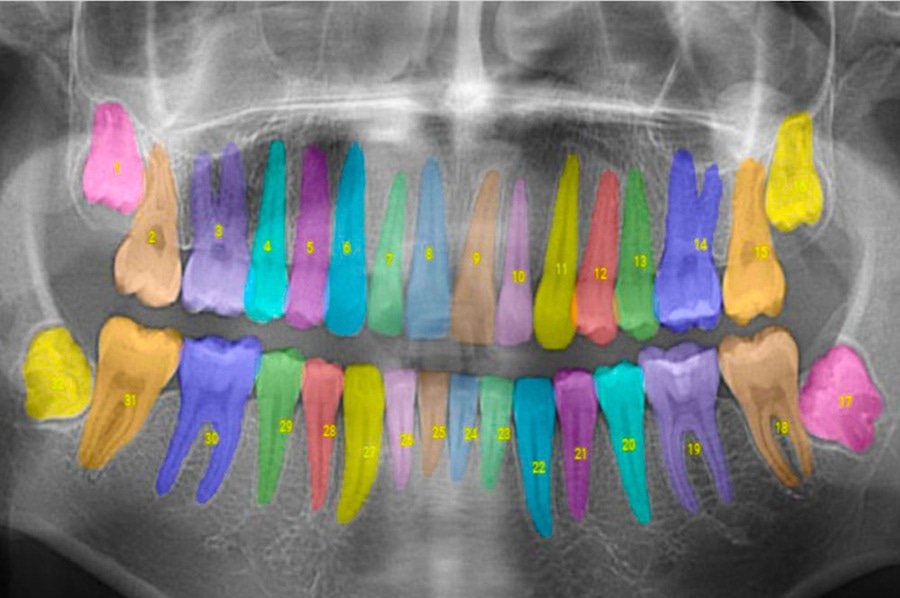

Image Credit: MIT, Courtesy of Overjet

Overjet’s software has the capacity to automatically analyze and annotate X-Ray images. When the image then appears on the screen, there will be information on the kind of X-Ray taken, how a tooth may be impacted, the precise level of bone loss with color overlays, the severity and location of specific cavities, etc. This provides dentists with a great deal of more information to offer patients when discussing the best available treatment options.